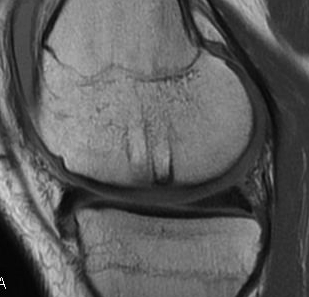

Technique Mosaicplasty Type 3 OCD

- MRI cartilage sequences at 3 and 6 months to assess cartilage healing